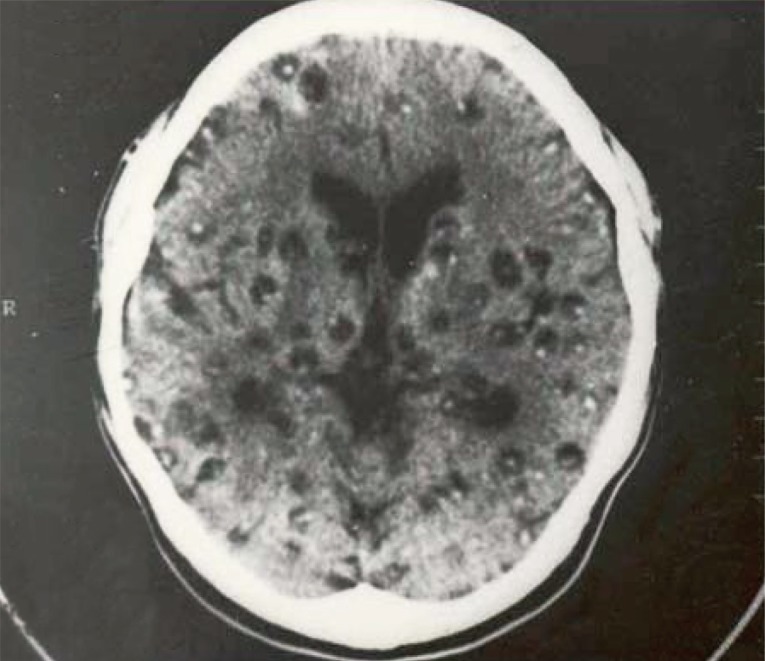

The major symptoms of human cysticercosis included headache 65.9-90.4%, epilepsy 56.4-67.5%, quickened muscle 35.3-48.9%, losing memories 42.4-46.9%, sleeplessness 40.3-46.4%, hearing disorders 36.4-42.4%, nausea/vomiting 39.2-40.8%, paralysis 28.4-30.8%, feeling disorder 18.2-20.1%, biopsy positives in subcutaneous tissues 92.2-95.4%, increased eosinophils 83.4-84.5%, positive ELISA with Taenia antigen 85.1-86.6%, and positive MRI/CT scan with live cysts in the brain 90.1-92.2% [8,10]. Subcutaneous cysts were found in back-chest 36.6%, hands 28.7%, head-face-neck 18.2%, and legs 17.4%. The highest number of subcutaneous nodules was 300 cysts in a patient (Fig. 3) [13]. Regarding the number of cysticercus cellulosae cysts in the brain, patients with <20 cysts were 53.3%, and those with ≥20 cysts was 46.7%. The highest number of cysticerci in the brain was 300 (Fig. 4) [13].